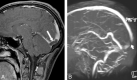

Twenty-five-year-old man with subacute thrombosis (thrombus age, 4 days) of posterior portion of superior sagittal sinus, torcular region, and right lateral sinus. Sagittal source image of static VIBE part of combo-4D MRV reveals large isointense filling defect within posterior portion of superior sagittal sinus extending into torcular area (long white arrow in A). On sagittal whole-brain MIP reconstructed image of 2D TOF MRV, most of this thrombus shows hyperintense signal intensity mimicking flow. The small vertical signal intensity gap (short white arrow in B) was misinterpreted as artifact on a single section derived from in-plane signal intensity loss (coronal acquisition). No flow signal intensity is depicted in thrombosed right lateral sinus.